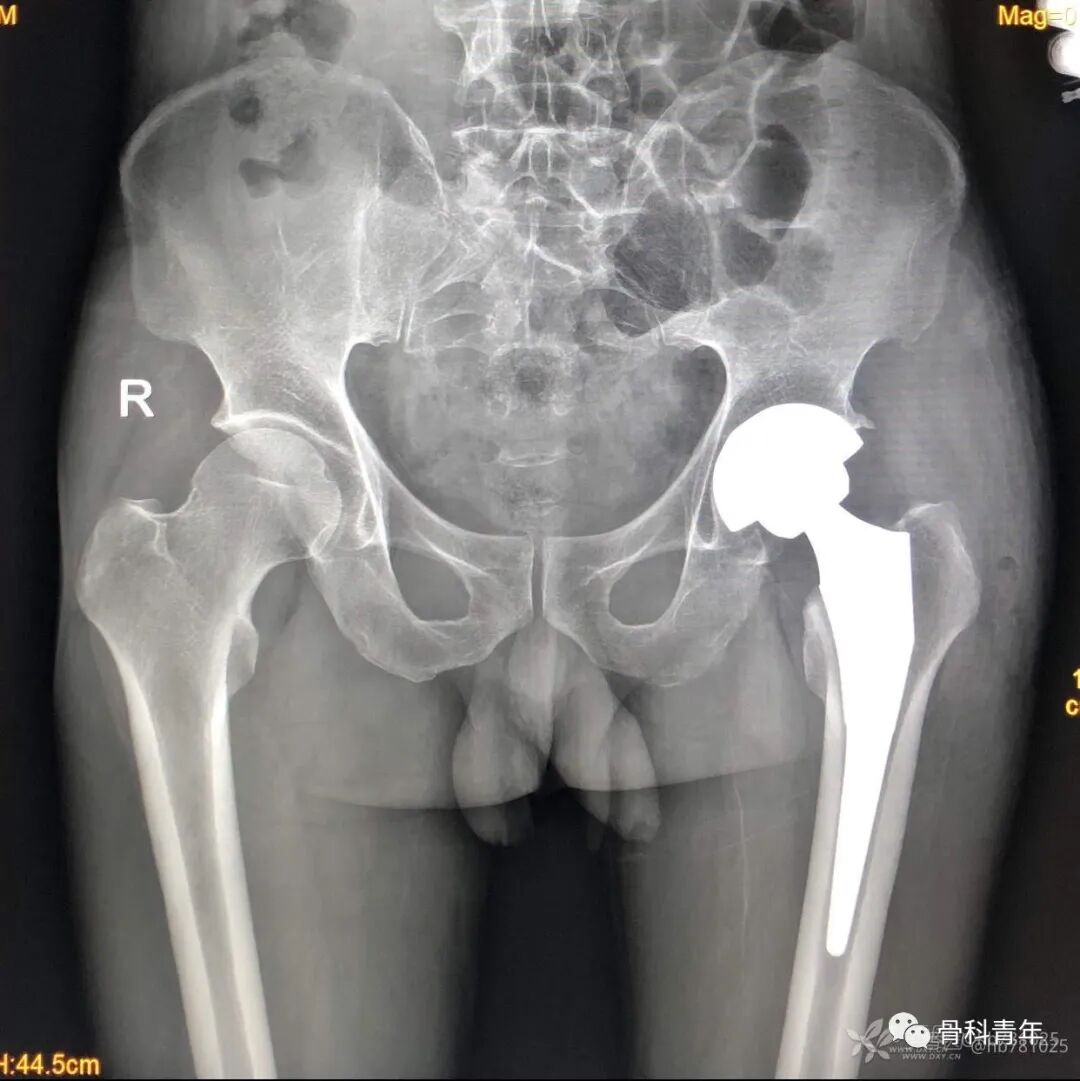

2.全髋关节置换